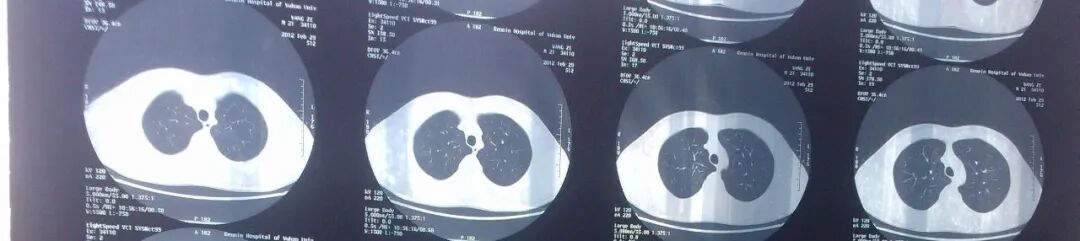

CT即电子计算机断层扫描,它是利用精确准直的X线束、γ射线、超声波等,与灵敏度极高的探测器一同围绕人体的某一部位作一个接一个的断面扫描,供完整的三维信息,具有扫描时间快,图像清晰等特点,可用于多种疾病的检查。

CT的辐射剂量相较于X光片大一点,普通健康体检检查尽量选择低剂量CT筛查而不是常规CT,怀孕妇女不宜进行CT检查。

1、普通平扫

即常规的CT检查,一般只需要躺在CT机上面进行扫描便可,无需打造影剂,速度快,方便简洁,故常作为初次检查、急性病变的首要检查方案。

胸部 肺、胸膜及纵膈各种肿瘤、肺结核、肺炎、支气管扩张、肺脓肿、囊肿、肺不张、气胸、骨折等;对于显示肺部病变有非常满意的效果,对肺部创伤、感染性病变、肿瘤等均匀有很高的诊断价值。对于纵隔内的肿物、淋巴结以及胸膜病变等的显示非常清晰也令人满意,可以显示肺内团块与纵隔关系等。

最常用X光片、CT大致了解选X光片,细致分析选CT肺的检查一般不选核磁

胸部